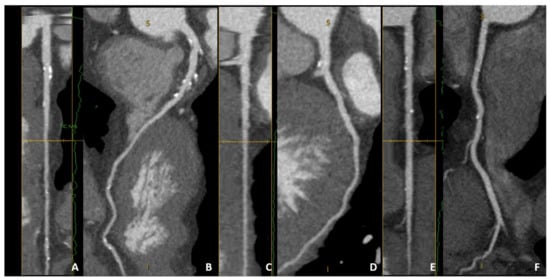

| Remodeling index (RI) | Ratio between lesion plaque area (red circle) and reference lumen area (blue circle). Positive remodeling is defined as RI > 1.1. | ![]() |

| Low-attenuation plaque (LAP) | Presence of any voxel < 30 HU in a coronary plaque. | ![]() |

| Plaque burden (PB) | Derived by the following formula: (lesion plaque area (red circle)—lesion lumen area (blue circle))/lesion plaque area (red circle). | ![]() |

| Napkin-ring sign (NRS) | Presence of rim-like thin enhancement (no more than 130 HU) distributed along the outer contour of the vessel and surrounding a fibro-lipidic plaque. | ![]() |

| Small spotty calcifications (SC) | Any discrete calcification ≤ 3 mm in length and occupying ≤ 90° arc when viewed on short axis. | ![]() |